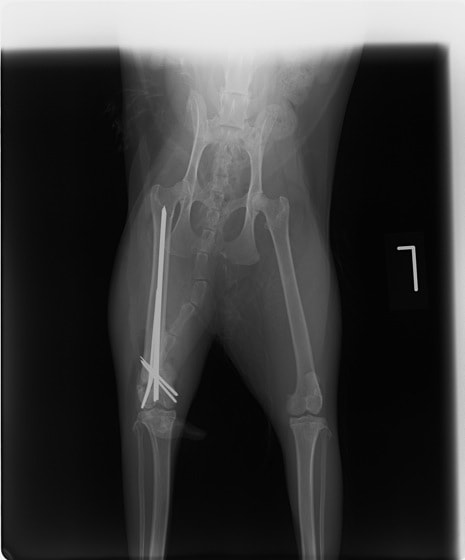

症例3:キルシュナーワイヤーのピンニングによる整復

ペルシャ猫 11ヶ月齢 雄

他院にて左大腿骨遠位の成長板骨折(salter-harrisⅠ型)が認められており、治療相談を目的として来院。当院にて、キルシュナーワイヤーを用いたピンニングにより骨折部位の整復を行いました。術後の経過は良好で、現在も経過観察中です。

術前レントゲン

術後レントゲン